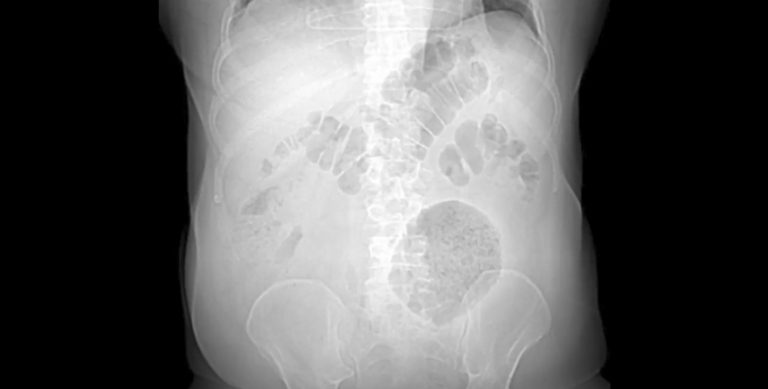

Um caso de divertículo gigante relatado pelo Hospital Municipal Salgado Filho (HMSF) foi apresentado no 17° Congresso Europeu Colorretal, realizado entre os dias 3 e 6 de dezembro de 2023 na cidade de St. Gallen, na Suíça. A descoberta reportada, uma formação inflamatória de 13 x 12 x 10cm na região abdominal, está entre os menos de 200 casos da doença catalogados pela literatura médica até hoje — em média, este tipo de inflamação tem entre 4 e 9cm de diâmetro. O paciente, um homem de 62 anos, foi operado no HMSF e está plenamente recuperado.

O caso de divertículo gigante chegou pela emergência do hospital. O paciente vinha sofrendo de dores abdominais e perda de peso — alguns dos sintomas mais comuns de divertículo — há pelo menos dois meses. Como informa o artigo publicado na renomada revista “European Surgery — Acta Chirurgica Austriaca”, assinado pela equipe do Hospital Salgado Filho, o exame clínico indicou a presença de uma massa flácida, palpável e dolorosa no flanco esquerdo do abdome. Ao ver o resultado da tomografia computadorizada, Leonardo Fiuza ficou incrédulo com o tamanho da inflamação.

Uma semana depois, a cirurgia de laparotomia exploradora confirmou a existência de massa inflamatória na parede abdominal e no cólon sigmoide, que fica na porção final do intestino grosso. O paciente teve uma recuperação tranquila e recebeu alta quatro dias depois.